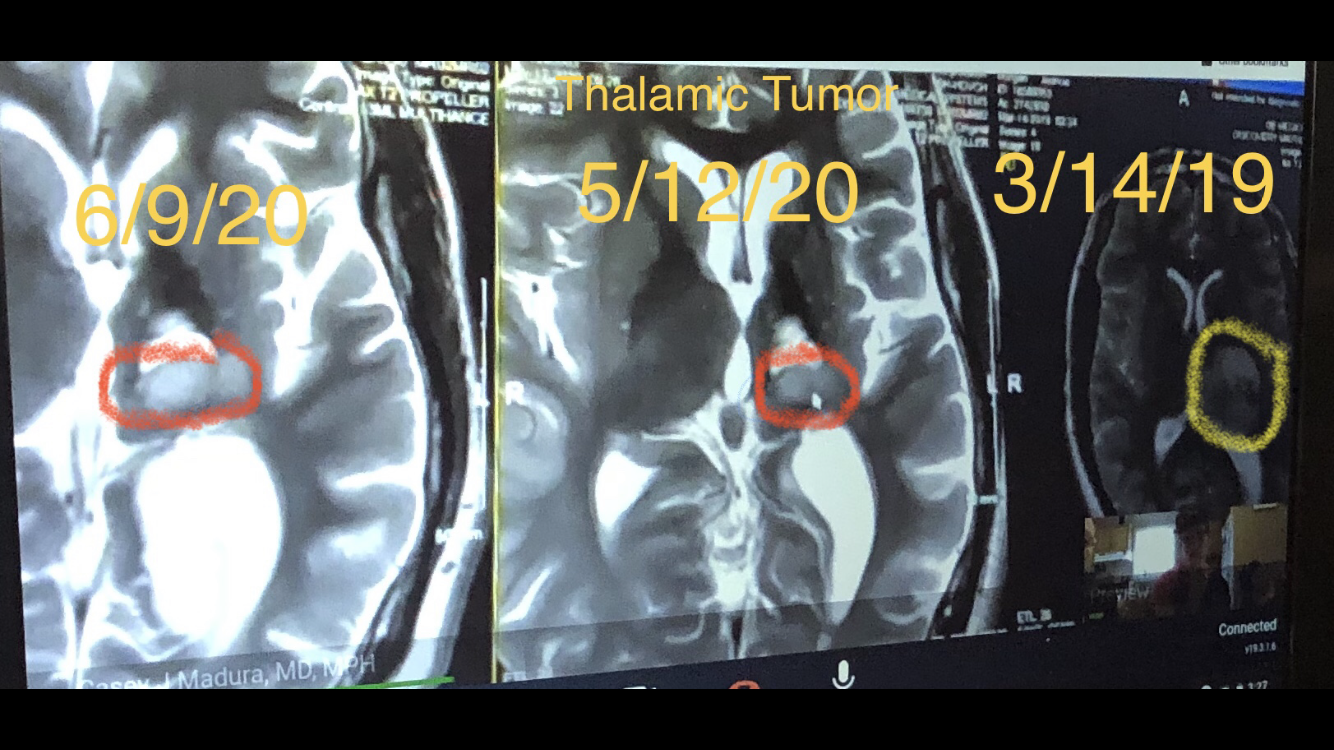

On Saturday, Josh returned to Devos Children’s Hospital in Grand Rapids for a more detailed MRI that his doctors hoped would give them a better understanding as to the whether the two new lesions in his brain (one in the original cavity located in his thalamus and the other located in his cerebellum) were a sign of tumor regrowth or if they might be a result of the radiation treatment he had last year. This MRI was our last opportunity to learn more in the hopes of avoiding a more invasive biopsy.

On Monday, we received a phone call from Josh’s oncologist with the results of the MRI. The images showed that the two lesions had grown significantly since his last scan 3 1/2 weeks ago. The growth combined with everything else doctors were seeing on the MRI helped them to conclude that we are indeed dealing with two new high grade gliomas (tumors.)

As surgery to remove the tumors would be difficult, particularly for the tumor located in the cerebellum, it was decided that Josh will be undergoing another round of radiation and chemotherapy. The radiation will be focused on both tumor areas which is a bit tricky as they need to be careful how much radiation the brain stem receives. It is not directly being treated but there is the possibility of it being subjected to some of the radiation. As the left side of his brain stem has possibly already been affected by the treatment last spring, they now need to be extra careful and therefore want to begin treatment while the tumor in the original area (posterior thalamus) is smaller. This will hopefully minimize the effects on the brain stem.

The goal of the treatment is to hopefully slow or stop the growth of the tumors or even better to see them shrink in size. Dr. Braunreiter was very clear that this treatment will not make the tumors “go away,” and that right now apart from surgery there isn’t any treatment that can do that, but trying to slow or stop the progression is an important step. We continue to have faith in our doctors and their guidance and we are very hopeful to see the results of this new treatment regimen.